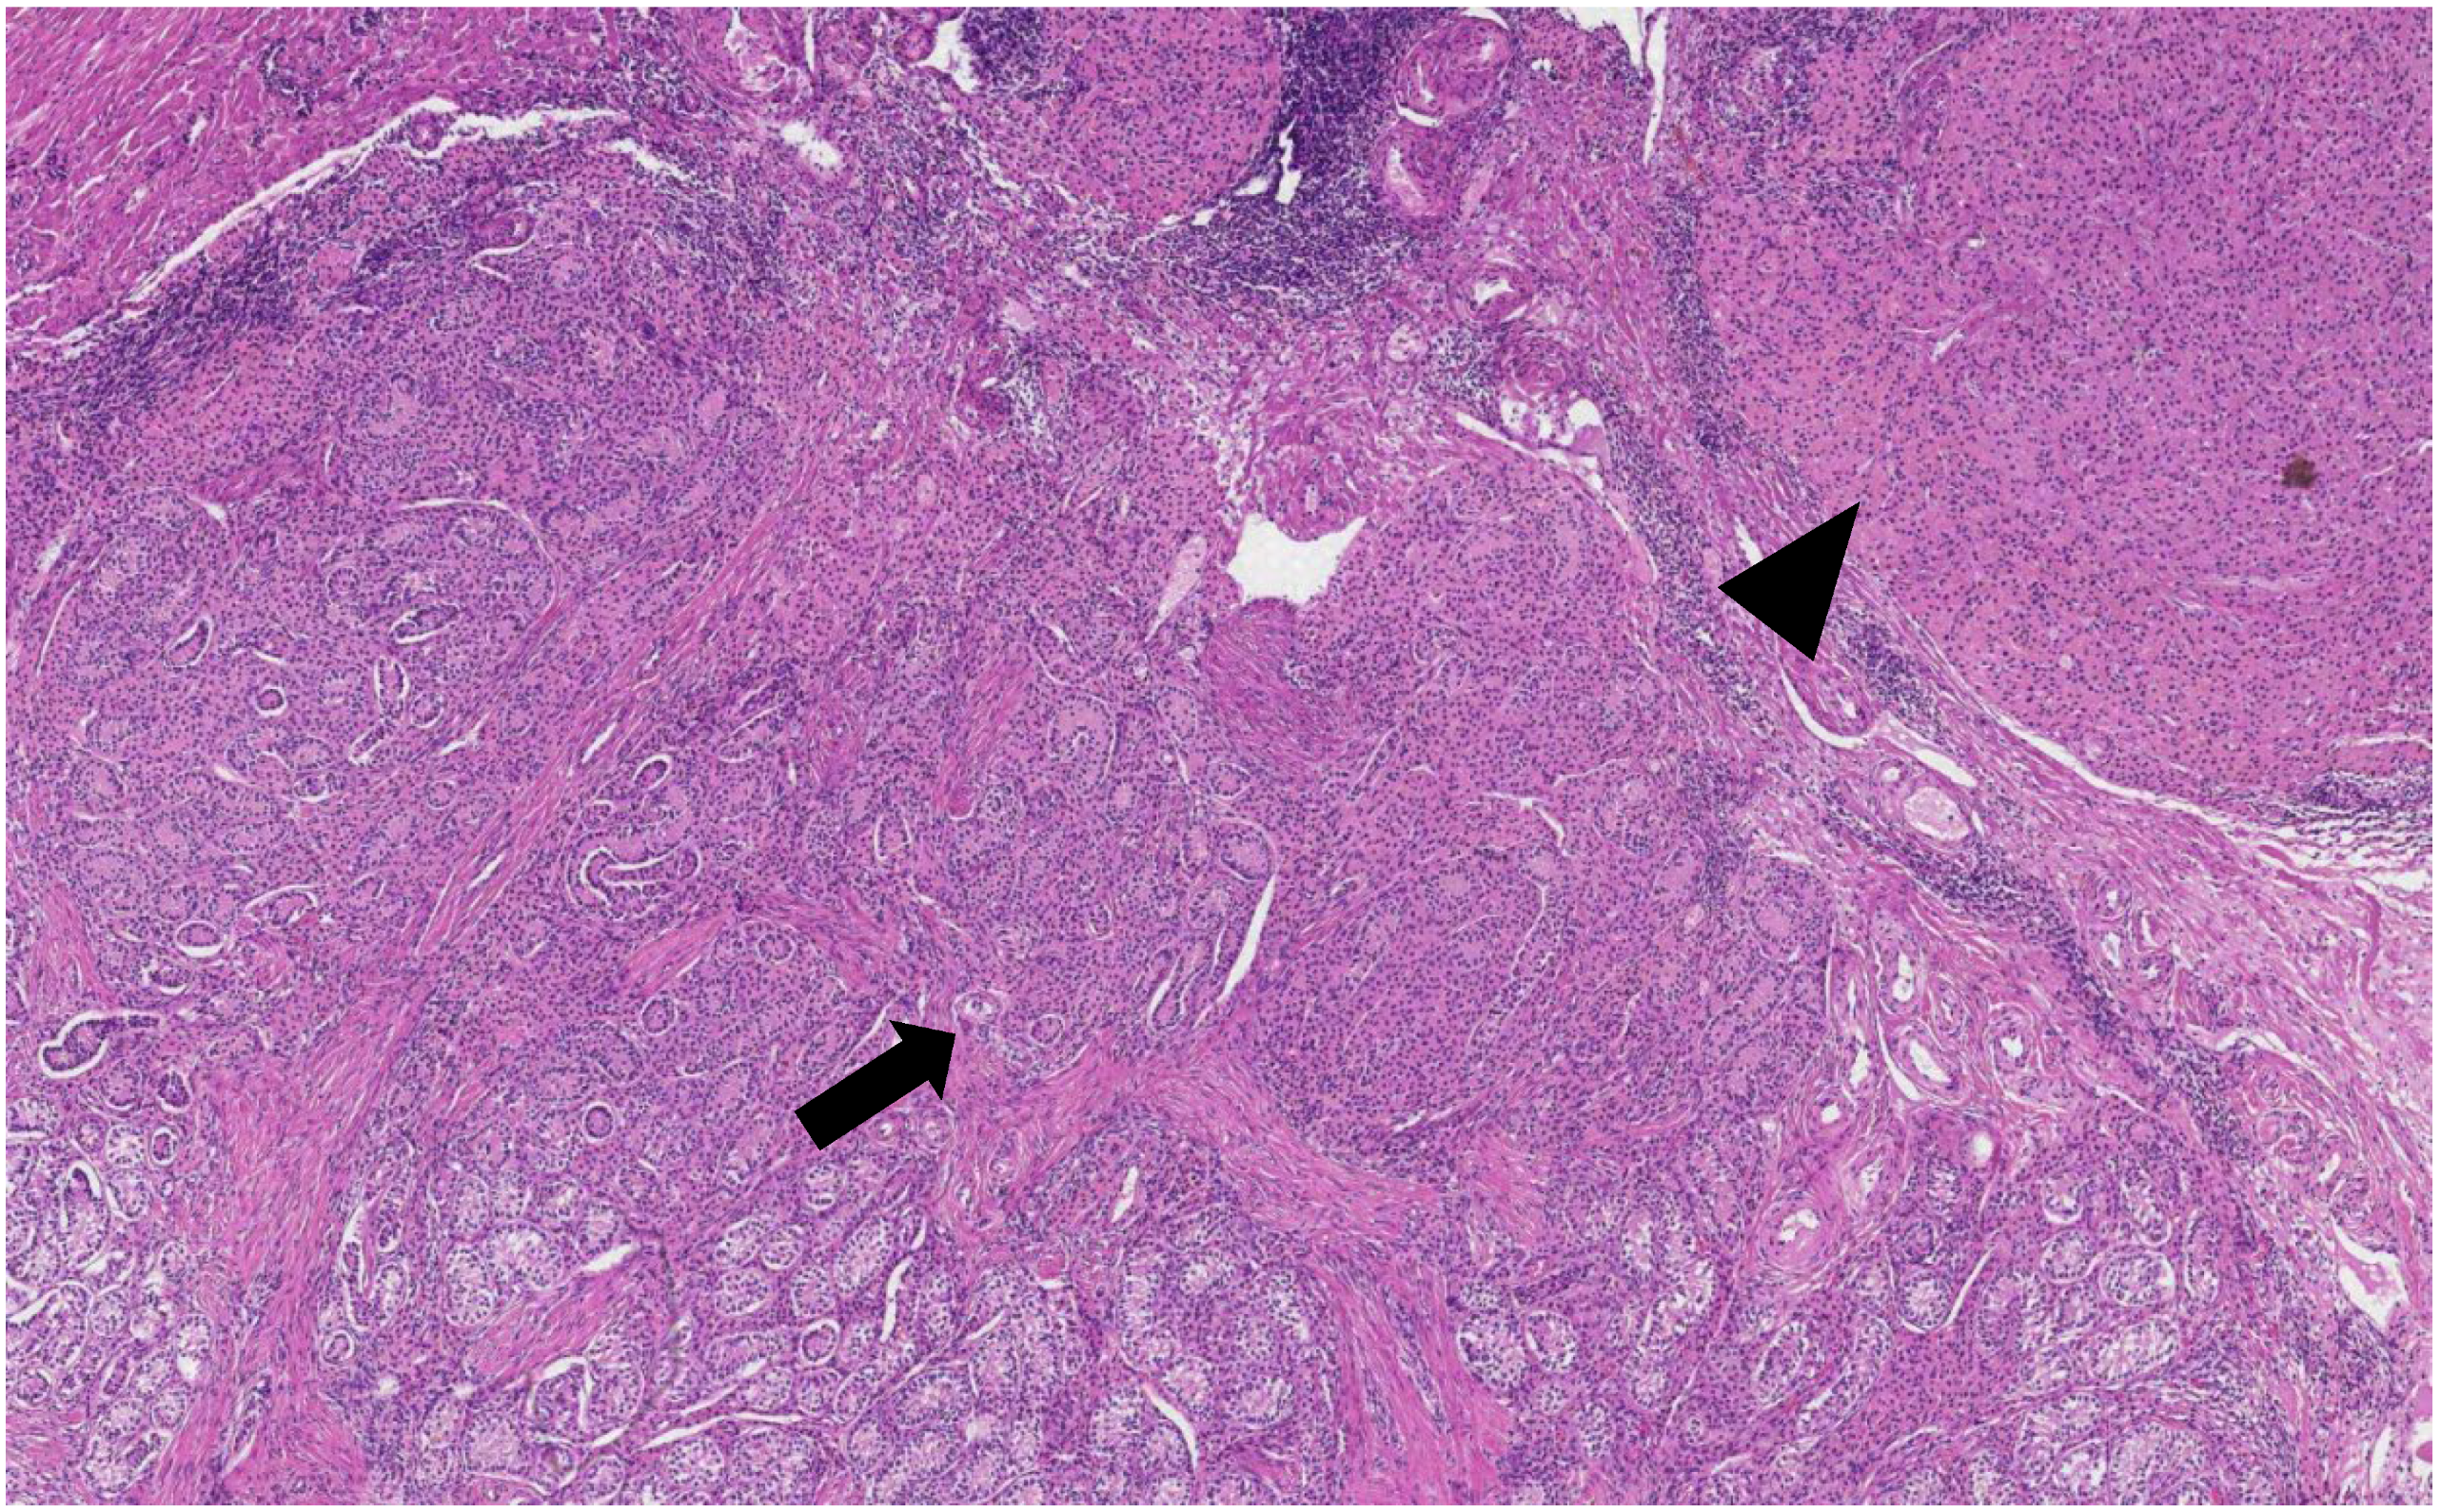

The histological analysis of the patient’s removed gonads revealed that there were hypoplastic testicles, which is a clinical sign of androgen insensitivity syndrome (Figure 3, Figure 4, Figure 5 and Figure 6). After the operation, testosterone analysis was repeated-hormone level significantly decreased to 0.83 nmol/L, which is a normal female-range value for a woman at that age.

Figure 6. One of the testes revealed a nodule composed of spindle cells, abundant collagen fibers and tubular structures lined by Sertoli cells (H&E staining, ×40).